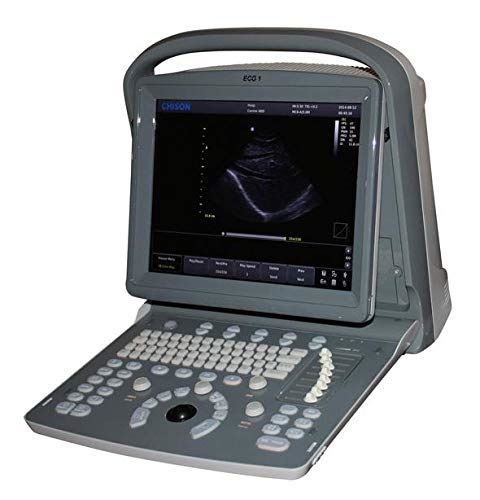

DIAGNOSTIC ULTRASOUND MACHINES FOR SALE